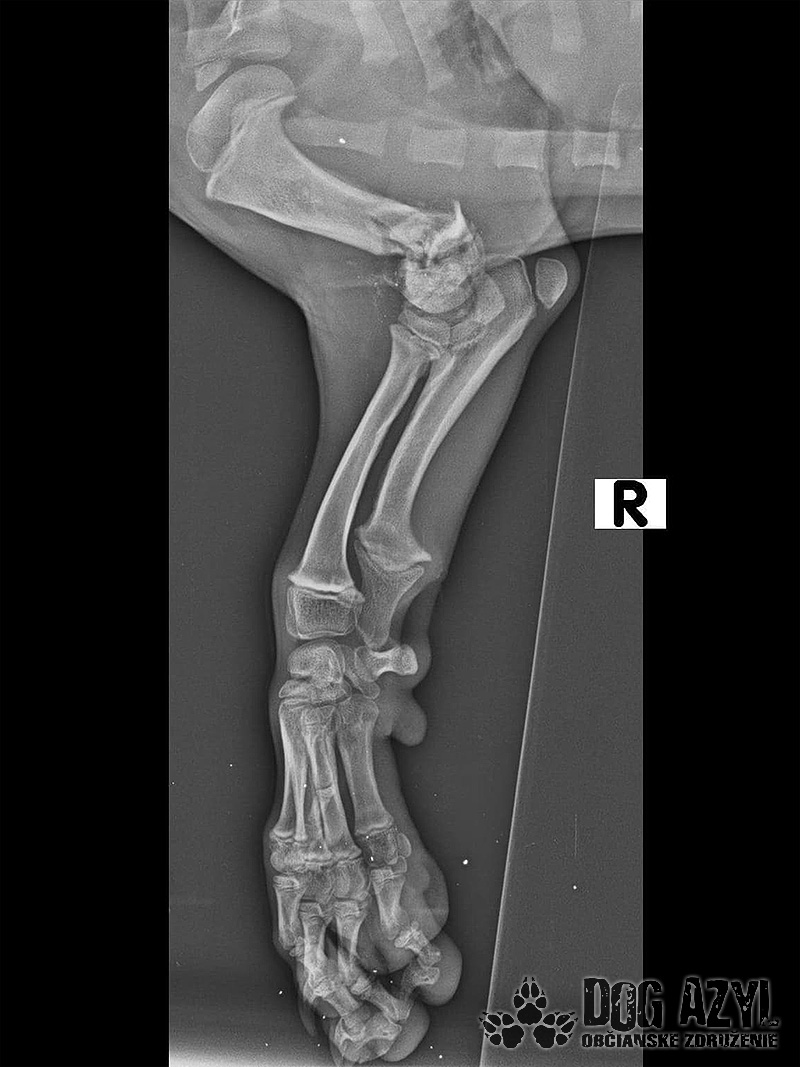

Pluto dnes absolvoval druhú operáciu. Vyberala sa platnička a veľká skrutka, ktorá sa nahradila menším pinom. Koncom mesiaca ho čaká ďalšia a dúfame, že už posledná operácia. Také malinké šteniatko a už toľko bolesti musí prežívať :( Má sa dobre, rastie do krásy a už sa pomaly može naplno šantiť so svojim kamošom v dočasnej opatere. :) Veľmi pekne prosíme, pomôžte nám s úhradou faktúr. Faktúry nájdete priebežne v galérii a na konci článku aj zoznam darcov s prijatou aj chýbajúcou sumou. Po poslednej operácii čakajú Pluta ešte mesiace rehabilitácie, aby sa nožička úplne rozhýbala a mohol ju používať naplno :)

Odoberal sa od drogovo závislých asociálov, ktorý boli vysťahovaný z domu. Ihly, striekačky, ľudské výkaly, rôzne neidentifikovateľné zvratky, špinavé oblečenie, použité kondómy - to všetko nahádzané na jednu kopu v obývačke, kde Pluto so svojou maminkou Miou žili. :( Nevieme ako sa to stalo, kto mu ublížil, ale Pluto má prestrelenú prednú nohu! Viete si predstaviť toho psychicky narušeného človeka, ktorý strieľa na malé bezbranné šteniatko? V dôsledku strelnej rany má doslova rozdrvenú lakťovú kosť. Mali sme veľké obavy, že o nožičku príde, ale MVDr. Vatolík s teamom veterinárnej kliniky Sibra centrum opäť urobil zázrak a malému nožičku napravil a prognóza je viac než dobrá. Čaká ho ešte dlhá cesta k zotaveniu, ale je to odvážny a statočný bojovník. Nechceme si ani len predstaviť čím všetkým si tie zvieratká muesli prejsť, a kto vie koľko ich pôvodne bolo.. Nikto nevie ako a kde skončili Plutovi súrodenci...